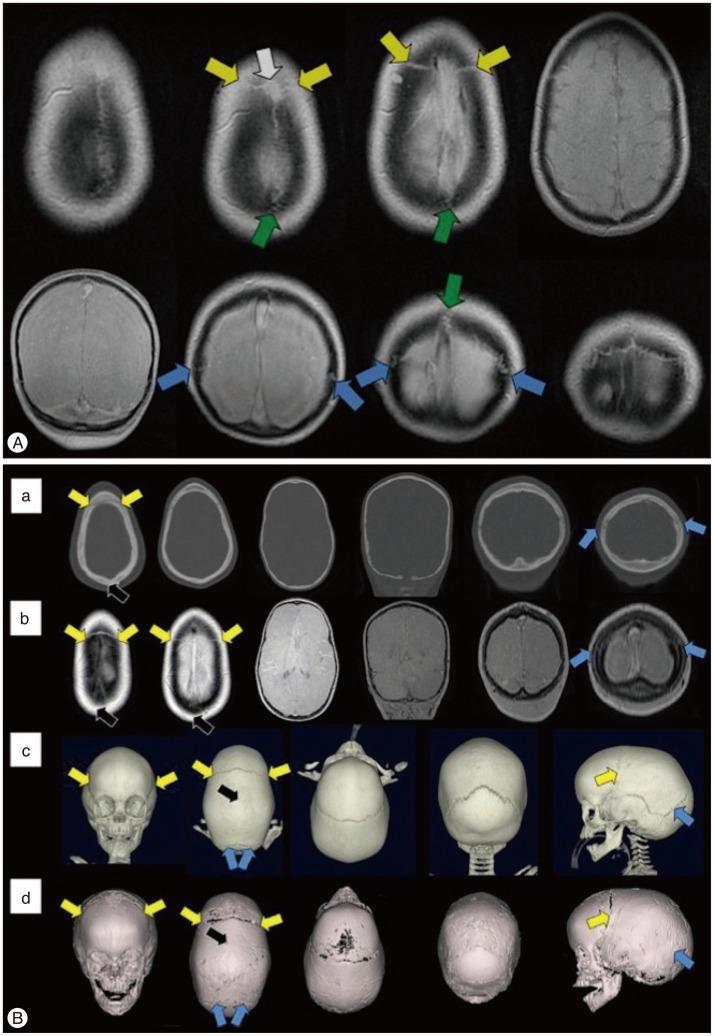

The purpose of this article is to review imaging findings and to discuss the optimal imaging methods for craniosynostosis. The discussion of imaging findings are focused on ultrasonography, plain radiography, magnetic resonance imaging and computed tomography with 3-dimensional reconstruction. We suggest a strategy for imaging work-up for the diagnosis, treatment planning and follow-up to minimize or avoid ionized radiation exposure to children by reviewing the current literature.

本文旨在回顾影像学表现,并讨论颅缝早闭的最佳影像学检查方法。影像学表现的讨论重点在于超声检查、X线平片、磁共振成像以及三维重建计算机断层扫描。通过回顾当前文献,我们提出了一种针对诊断、治疗规划及随访的影像学检查策略,以尽量减少或避免儿童受到电离辐射。